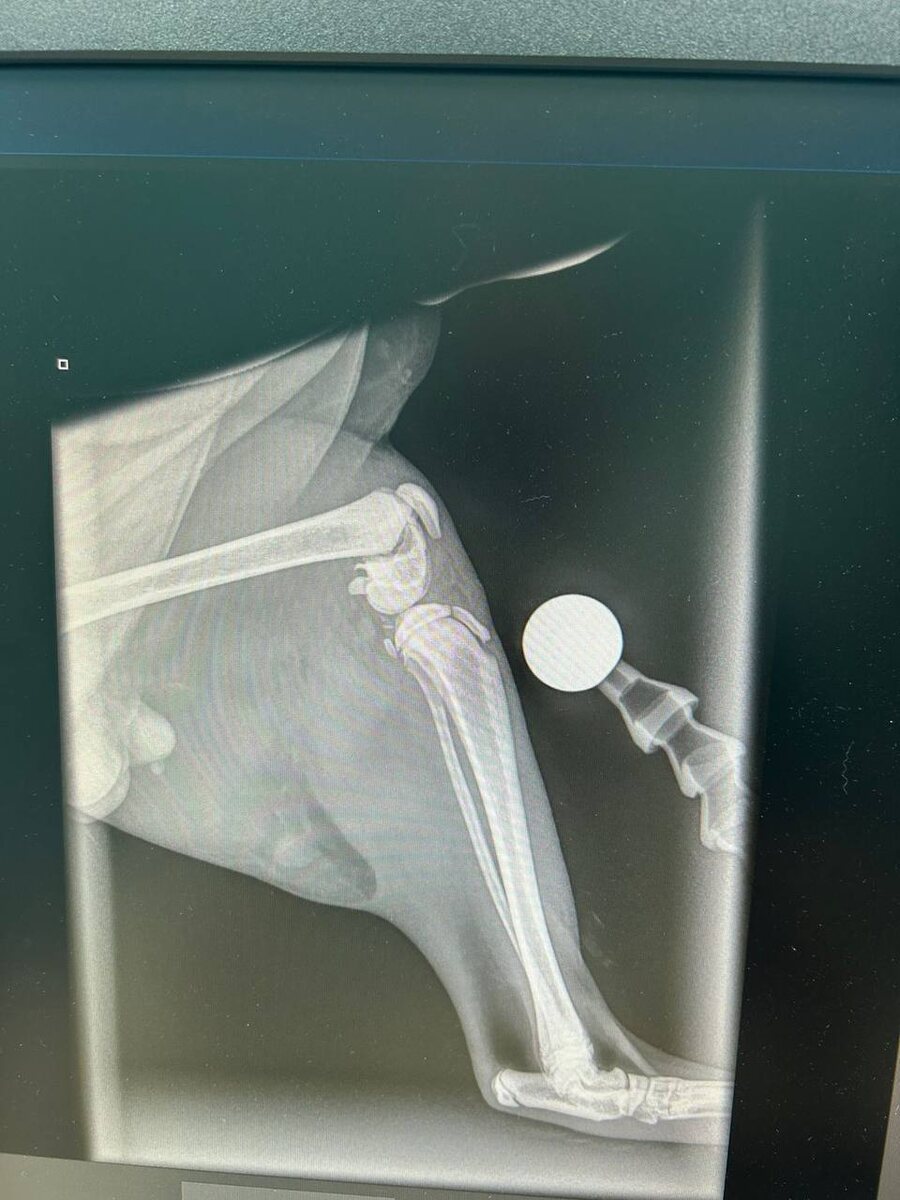

Кузе только что закончили делать операцию !

Ник поставили спицы в бедро(фото прилагаю) сразу кастрировали!